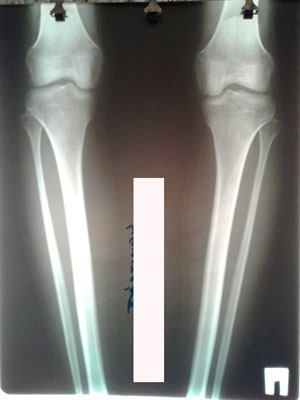

Исходник - 22 года.

Дата операции - 04.08.2020

Вложения

image-04-08-20-09-38-4.jpg

image-04-08-20-09-38.jpg